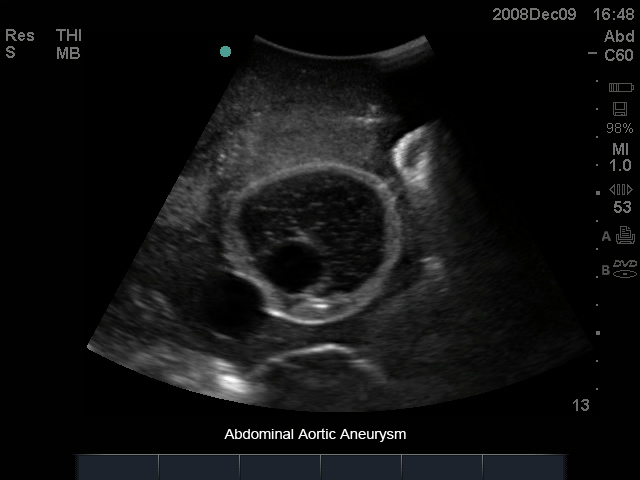

腹主动脉瘤超声训练模型

型号:PC-BP004

模型数据源于真实成人躯干模型,具有腹主动脉瘤和相应血管的内在解剖结构,可用于培训临床医生对腹部主动脉瘤进行超声探查、获取标准切面、测量大小等操作